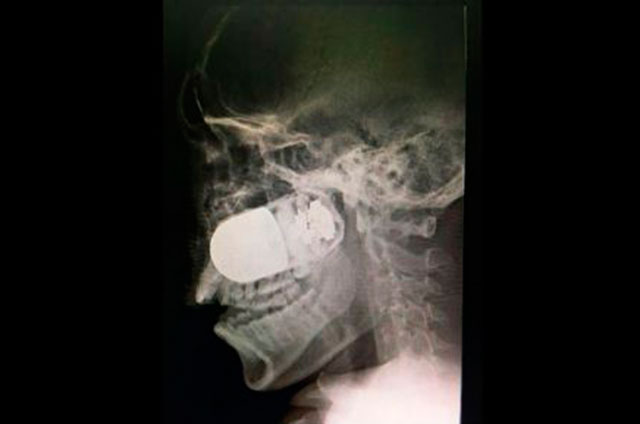

La cirugía para extraer una granada de asalto incrustada en el rostro de un soldado colombiano es un hecho excepcional y único en el mundo, porque estuvo en riesgo la vida del paciente y de todo el equipo médico del Hospital Militar Central, en esta capital.

El médico jefe de cirugías del Hospital Militar Central, William Sánchez, explicó a la prensa local que el soldado Leandro José Luna llegó el domingo pasado al centro hospitalario procedente del departamento de Arauca, en el suroccidente del país, por vía terrestre, ante la imposibilidad de trasladarlo en avión.

Explicó que el soldado no podía ser trasladado vía aérea por el riesgo que explotara la granada de asalto M40, que tenía incrustada en el rostro. Por esta razón fue movilizado en una ambulancia durante un recorrido de más de ocho horas.

El pasado fin de semana, el soldado estaba patrullando en las inmediaciones del río Tame, Arauca, cuando unos de sus compañeros activó en forma accidental un lanzagranadas MGL, y como consecuencia una granada se le incrustó en el rostro de Luna.

El militar “llegó en estado crítico al hospital y se tomó la decisión de atender con rapidez al paciente. El equipo quirúrgico tenía un riesgo muy elevado”, señaló Sánchez.

Insistió que este es un caso inusual, único a nivel mundial, porque se tuvo que montar todo el dispositivo médico para la cirugía en el estacionamiento a cielo abierto del Hospital Militar Central, con apoyo de expertos en explosivos para tener controlada la granada.

Fue una intervención de altísimo riesgo para el paciente y el equipo médico por el alto poder explosivo que tienen las granadas de asalto, que son utilizadas en la confrontación armada que vive este país desde hace 52 años de guerra.

Después de la exitosa intervención, el soldado se encuentra estable y en recuperación.